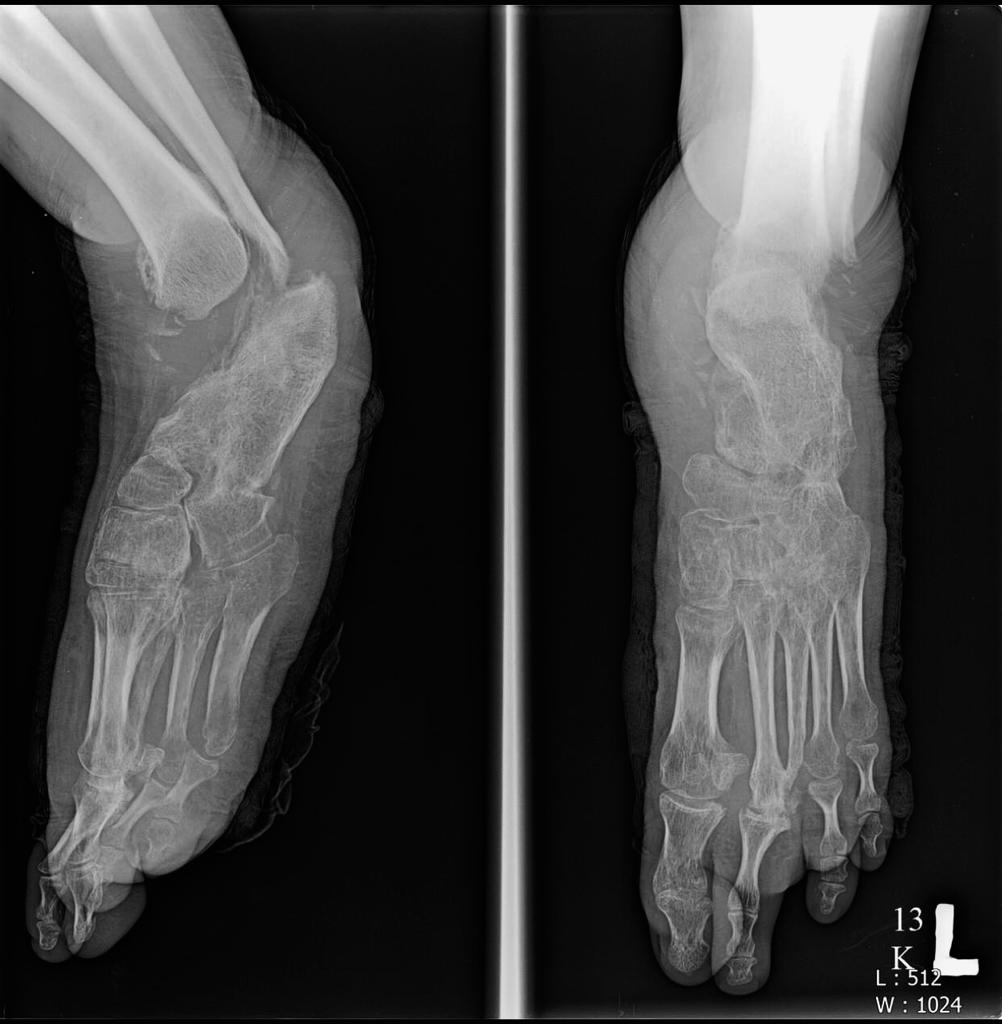

Charcot joint, also known as a neuropathic joint or Charcot (neuro/osteo)arthropathy, refers to a progressive degenerative/destructive joint disorder in patients with abnormal pain sensation and proprioception.

In modern Western societies by far the most common cause of Charcot joints is diabetes mellitus, and therefore, the demographics of patients matches those of older diabetics.

Unlike septic arthritis, Charcot joints although swollen are normal temperature without elevated inflammatory markers. Importantly, they are painless.

Charcot joints are typically unilateral but are bilateral in ~20% (range 5.9-39.3%) of cases.

In the presented case there are destruction of talar head and neck with dislocation of talo-navicular joint, resorption of midfoot bones, subchondral sclerosis and multiple subchondral cysts on talocalcaneal aspect and cuboid facet of the calcaneum, progressive decrease of calcaneal inclination with typical rocker-bottom deformity, soft tissue swelling and arterial calcification. Bony debris are seen on dorsal aspect of the foot and posterior ankle joint. All findings are suggestive of Charcot neuro-osteoarthopathy, which is primarily an articular disease and most commonly located in the midfoot.

Unlike osteomyelitis, Charcot neuroarthropathy is primarily an articular disease and not related to overlying skin or soft tissue changes. Charcot neuroarthropathy commonly involves multiple midfoot bones. Features include joint instability, dislocation, destruction, disorganization, increased bone density, joint debris and deformity. Presence of subchondral cysts and intraarticular bodies with absence of the secondary signs for osteomyelitis support neuroarthropathy without infection.